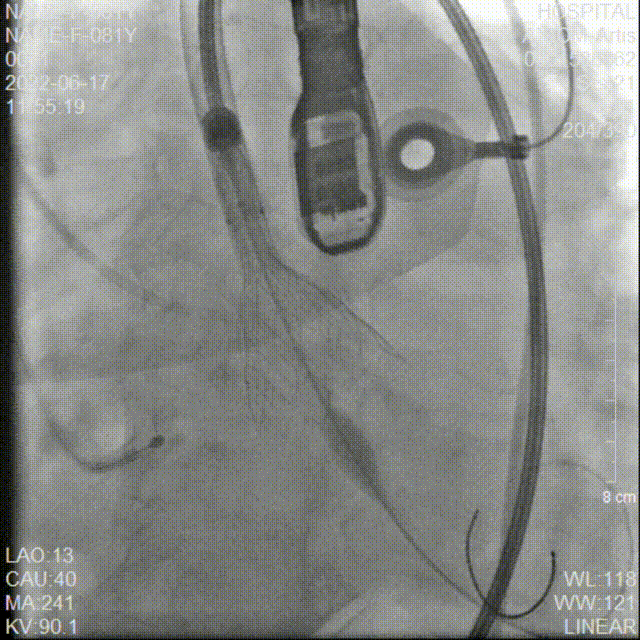

冠脉造影检查

术中20mm球囊预扩可见明显腰征,没有瓣周漏,双侧冠脉灌注情况良好,随后选择AV26瓣膜。TaurusElite AV26瓣膜送至主动脉弓,输送系统轻松过弓及跨瓣。